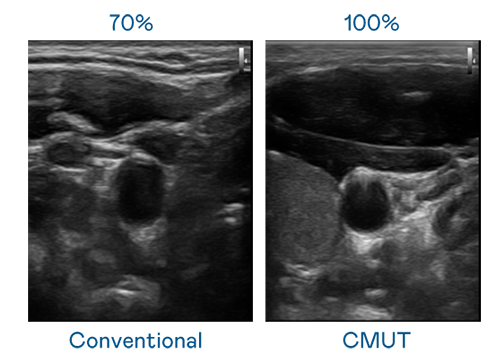

申博太陽(yáng)城運(yùn)用 TFT 陣列 (Array) 制程延伸尖端感測(cè)技術(shù) ,開發(fā)出多種感測(cè)元件的產(chǎn)品。高解析度、品質(zhì)穩(wěn)定且可量產(chǎn)的 CMUT 元件 ,可制作高解析度超音波探頭 、貼片型探頭 ,對(duì)病患實(shí)施精準(zhǔn)檢測(cè)與長(zhǎng)時(shí)間生理監(jiān)測(cè) 。為滿足 X光設(shè)備輕量化、可移動(dòng) ,甚至需針對(duì)待測(cè)物進(jìn)行外觀客制化的新需求 ,申博太陽(yáng)城結(jié)合非晶矽 (a-Si) 制程與新的封裝技術(shù) ,實(shí)現(xiàn)可撓曲、具優(yōu)異 TFT 遷移率 (mobility) 的柔性 X光感測(cè)器。目前也已提供完整玻璃和曲面型 X光感測(cè)器檢測(cè)解決方案 。